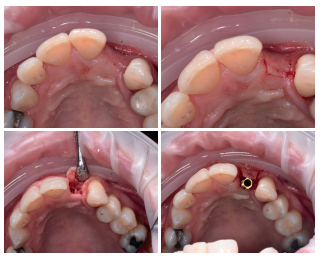

Se planificó la exodoncia del 2.2, para colocar un implante inmediato post-extracción, solicitando el consentimiento informado a la paciente. Una vez obtenido, se procedió a realizar un bloqueo anestésico mediante técnica infiltrativa con articaína al 4% con adrenalina 1:100.000 del nervio alveolar superior anterior, y nasopalatino. Se realizó la extracción forma atraumática y el fresado en una posición palatina, para favorecer la restauración implantosoportada posterior (Figura 5).

Tras la extracción, se separó en primer lugar la corona de la raíz, y se dividió la raíz en dos fragmentos, para poder retirar la gutapercha intrarradicular. Mediante el dispositivo Smart Dentin Grinder® (Kometa Bio. Bioner, España), se obtuvo un injerto con un tamaño de partícula de 300-1200 micrómetros, tras un tiempo de procesado total de 15 minutos (Figura 6).

Se colocó el injerto entre la superficie vestibular del implante, y la cortical vestibular, para cubrir el injerto con una esponja de fibrina (Gelatamp®) y dar dos puntos simples de sutura con poliamida no absorbible de 4/0 (Supramid®), realizando una radiografía periapical en el post-operatorio inmediato, para verificar la colocación adecuada del implante y del material de injerto (Figura 7). Así mismo, y con el objetivo de valorar el mantenimiento de la cortical vestibular se realizó un escáner de haz cónico realizado en el post-operatorio inmediato (Figura 8).

herida (B), radiografía periapical en el post-operatorio inmediato (C).

de dentina rellenando el gap.